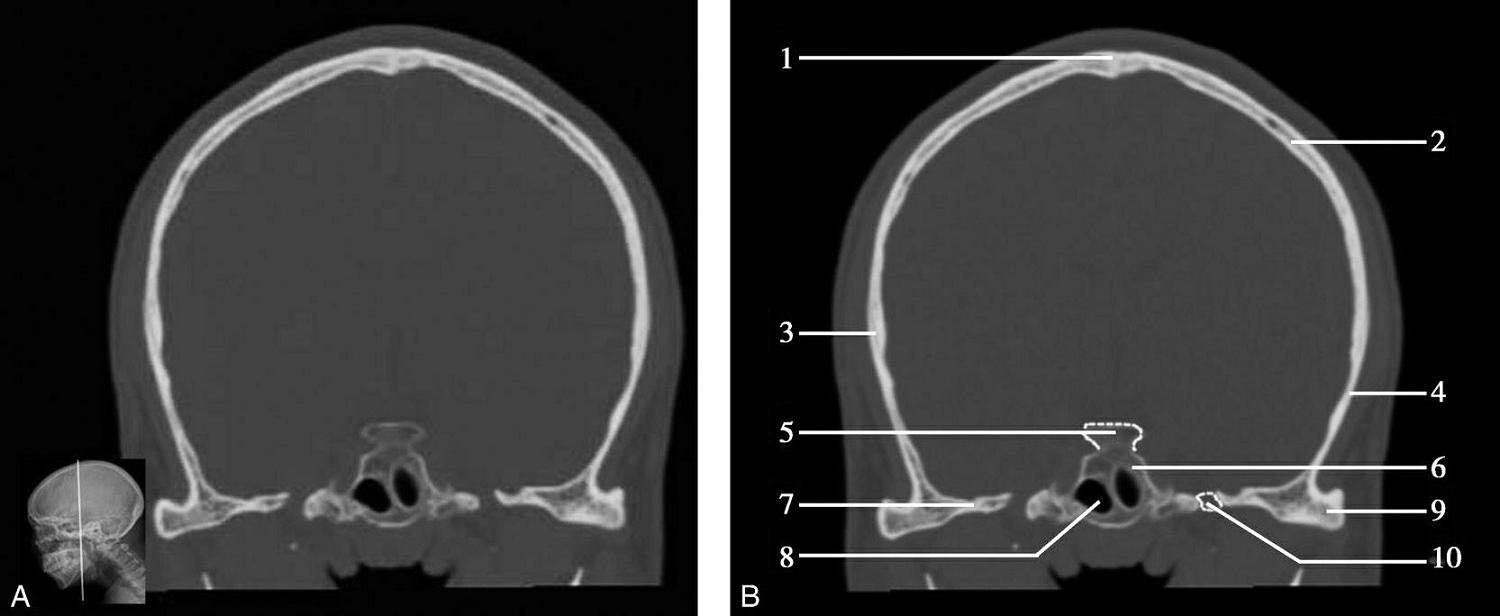

图1-2-2 颅底层面(骨窗)

A.横断面;B.横断面标注

1.鼻骨;2.筛窦纸板;3.颧骨眶突;4.翼腭窝;5.蝶骨大翼;6.卵圆孔;7.破裂孔;8.颞骨颧突;9.棘孔;10.斜坡;11.颞骨岩部;12.乳突;13.颈静脉孔;14.枕乳突缝;15.枕骨;16.枕内隆凸